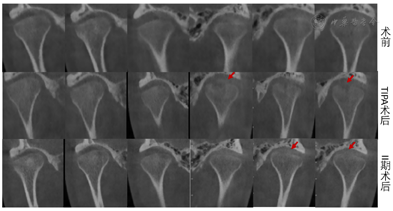

CBCT牙齿截图显示:上下前牙未见明显牙根吸收,上下前牙牙根位于骨松质内(图7)。关节截面显示:TIPA治疗后髁突表面发生功能性改建;髁突位置发生后退,关节窝随之发生相应改建。Ⅱ期治疗后髁突位置稳定,关节间隙恢复正常(图8,图9,图10)。治疗前、中、后头影测量结果见表1,矫治器前后头影描绘重叠图见图11。

2.TIPA是一种新型的功能矫治器[3],主要结构是双侧后牙合垫区由前下后上的两长斜导面组成,利用咀嚼力"渐进式"逐渐诱导下颌骨(骨、牙槽骨、牙)向后运动、上颌骨(骨、牙槽骨、牙)向前运动以及诱导髁突、关节窝发生生理性改建(图9、图10)。相较于头帽-颏兜(Facemask,FM)、Frankel Ⅲ(FR Ⅲ)、反式Twin Block(RTB)、双阻板磁力矫治器、骨性支抗弹性牵引等传统早期矫治装置,其主要针对于以下颌发育过度为主的骨性Ⅲ类生长期错合畸形,独有的长斜面结构有利于咀嚼、前伸和侧方运动,力更接近生理性,患者易适应和配合,且不要求后退下颌重建上下颌位关系,制作简单。术后患者矫治效果良好,锥形束CT重叠观察到髁突及关节后区发生生理性改建(图10),这与笔者团队的之前TIPA能持续性引起关节区不同区域的不同改建的研究一致[4,5,6]。